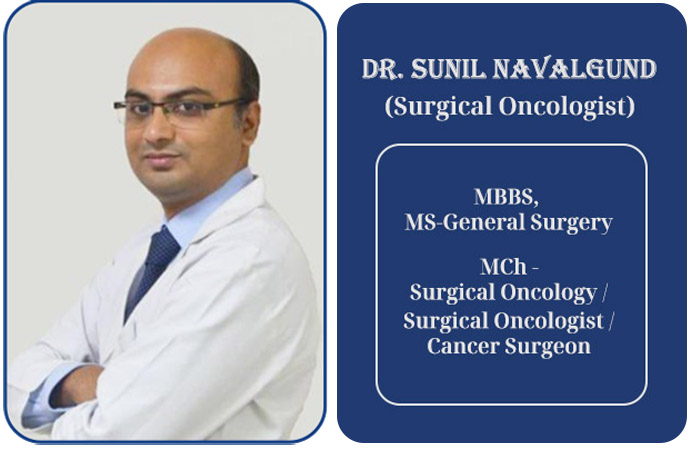

Dr. Sunil Navalgund, a highly skilled surgical oncologist, trained at the renowned Tata Memorial Hospital, Mumbai, has over 10 years of experience in oncology. He specializes in minimally invasive and robotic cancer surgeries, offering cutting-edge technologies to ensure optimal patient outcomes. Dr. Navalgund completed his undergraduate studies at Shri BM Patil Medical College, Bijapur, and post-graduation at Vijayanagar Institute of Medical Sciences, Bellary, before earning his M.Ch in Surgical Oncology from Tata Memorial Hospital, where he gained expertise across all surgical oncology subspecialties.

Currently a consultant surgical oncologist at Apollo Hospitals, Bangalore, since 2018, Dr. Navalgund is dedicated to improving cancer care. His practice focuses on advanced techniques such as oncoplasty for breast cancer, organ-preserving surgeries, and laparoscopic and robotic procedures, ensuring high-quality, patient-centered care.

With 10+ years of experience, specializes in minimally invasive and robotic cancer surgeries. He trained at Tata Memorial Hospital and holds an M.Ch in Surgical Oncology.